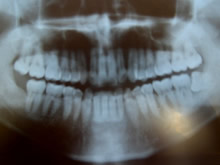

| 健康なパノラマX線写真 | 左下8 親知らず 抜歯適応症例 上顎8は抜かなくても良いケース |

| 健康なパノラマX線写真 |

| 左下8 親知らず 抜歯適応症例 上顎8は抜かなくても良いケース |